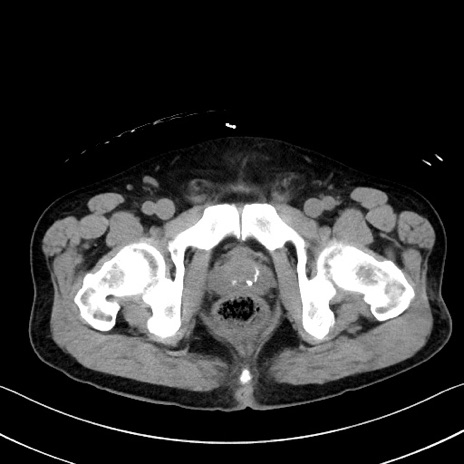

冠状断像

症例35(横断像)

【症例】70歳代 男性

【主訴】腹部膨満、嘔吐

【現病歴】昨日より腹部膨満感出現。本日増悪し、仙痛出現。嘔吐あり、受診。

【既往歴】糖尿病、胆摘後

【身体所見】BP 149/80mmHg、HR 74/min、BT 35.9℃、腹部:膨満、軟、圧痛なし。腸雑音減弱あり。上腹部正中切開瘢痕あり。

【データ】WBC 13500、CRP 1.72